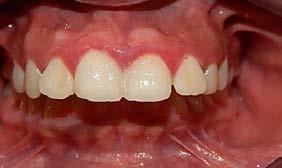

Figura 3. Lateral derecha. Figura 4. Izquierda de inicio. Figura 5. Frente. Figura 6. Overjet, laterales derecha e izquierda.

Las fotografías intraorales muestran las relaciones molares clase II y las relaciones caninas clase II bilaterales (Figura 3 y 4), espaciamiento anterosuperior, un overjet y overbite aumentado (Figura 5). La forma de los arcos es cuadrada, superior e inferior, con el apiñamiento moderado inferior y los espacios en superior.